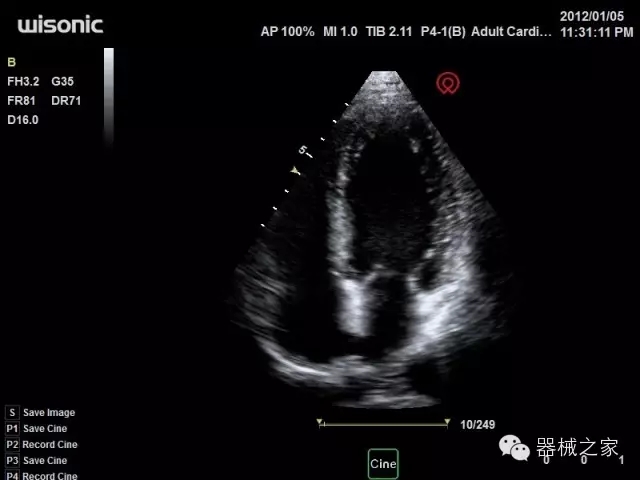

臨床圖片賞析

產(chǎn)品特點

·全球目前唯一一款配備主機(jī)雙探頭接口,整機(jī)重量(含電池)在5公斤以內(nèi)的便攜式彩超;

·一款互聯(lián)網(wǎng)彩超,只要有手機(jī)信號的地方就可以非常方便地實現(xiàn)遠(yuǎn)程會診和病案調(diào)??;

·鎂鋁合金外殼,堅固可靠耐用;

·獨有的HoloTM PW 實時3取樣門PW成像技術(shù),精確進(jìn)行血管診斷;

·一鍵優(yōu)化B、Color、PW,Auto Doppler自動識別血管位置、偏轉(zhuǎn)角度等,提高工作效率;

·30°超廣角精細(xì)偏轉(zhuǎn)成像技術(shù),更優(yōu)異的頻譜圖像;

·W+智能搜索引擎,快速尋找圖像;

·SSD、USB3.0保障開機(jī)快,導(dǎo)出圖像更快,減少等待時間;

·WIFI、網(wǎng)口、3G,多重聯(lián)網(wǎng)方式,全天候保障云端備份,不再擔(dān)心圖像丟失;

·粵械注準(zhǔn)201522231208